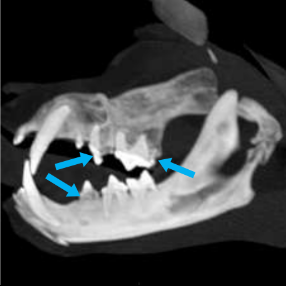

しかし数日後、再び貧血の進行が認められ原因究明と治療を急ぐ必要があったため、麻酔下にて出血点の精査のためのCT検査と内視鏡検査、歯肉炎に対して歯科処置(抜歯)を行いました。

CT検査にて歯肉炎に伴った破歯吸収病巣(歯が溶けた状態)が疑われましたが、それ以外の出血の原因となる病変は認められませんでした。

口腔内では歯石を除去した領域で破歯吸収病巣が認められ、抜歯と縫合を実施しました。

写真は上顎ですが下顎の病変も同様に処置しています。